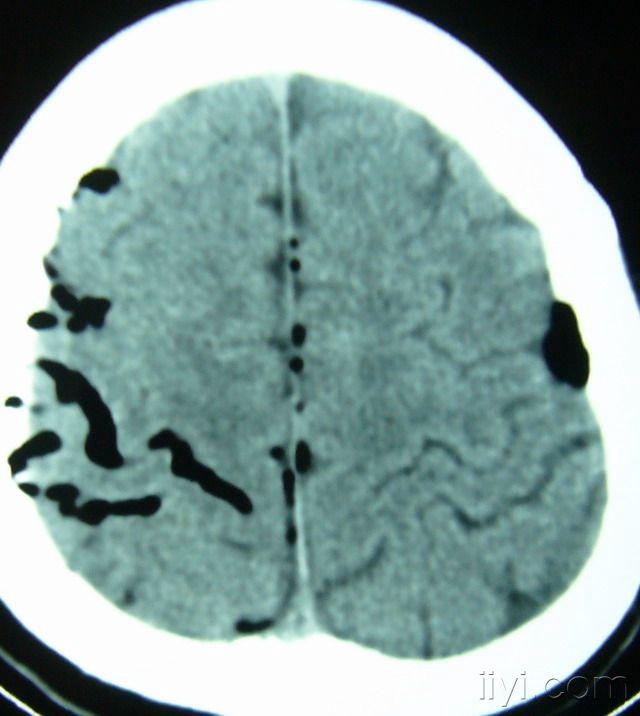

广泛气颅,颅底骨折 3.急症行